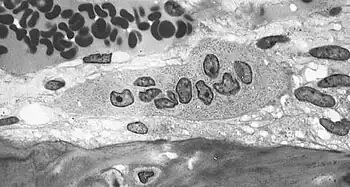

Light micrograph of an osteoclast displaying typical distinguishing characteristics: a large cell with multiple nuclei and a "foamy" cytosol.

Light micrograph of osteoblasts, several displaying a prominent Golgi apparatus, actively synthesizing osteoid containing two osteocytes.